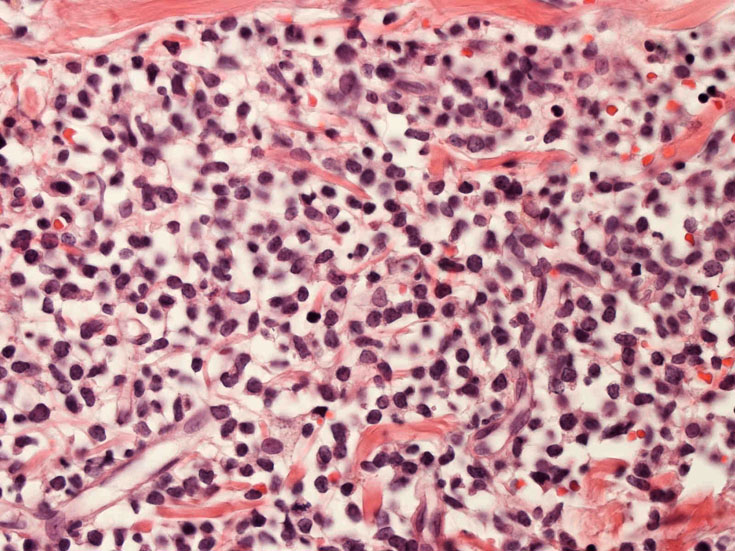

罹患リンパ節の基本構造は消失し腫瘍細胞のびまん性増殖で置換されている。非腫瘍性の小リンパ球(CD3+, CD4/8+)が濾胞様に散在して残る(Fig.01)。不整型または類円形の明るい核をもつmedium-sizeのリンパ球様細胞が密に増殖している。細胞質は乏しい(Fig.02)。CD68陽性macrophageが多く混在する部分が認められた(Fig.03)。

Fig.01Fig.02Fig.03